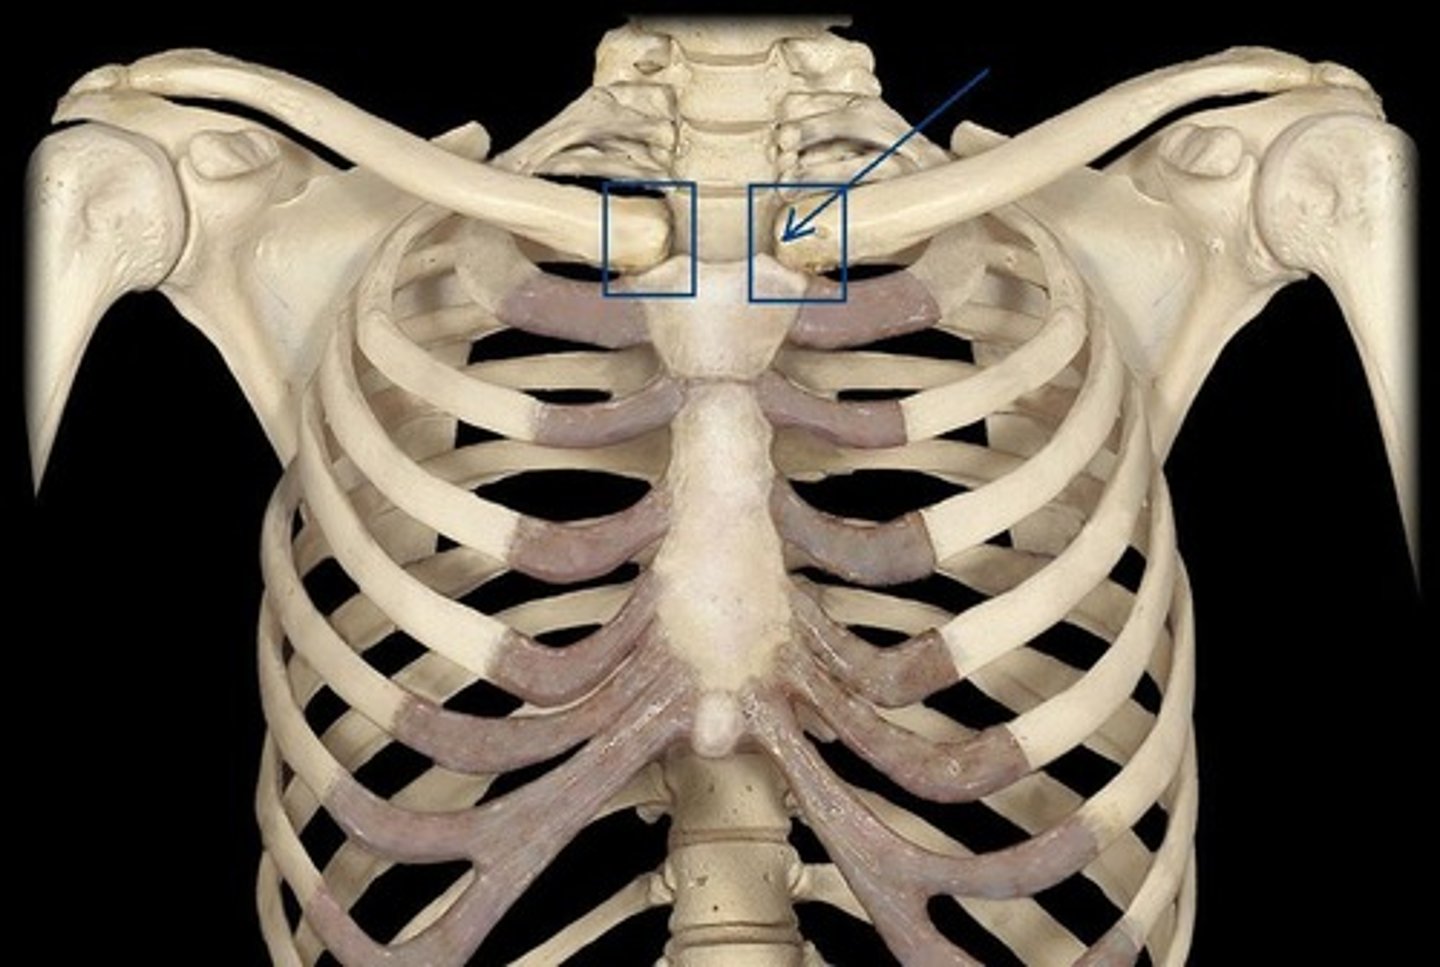

Sternoclavicular joint

Articulation between the clavicle and the sternum (saddle joint)

Acromioclavicular joint

the joint where the acromion and the clavicle meet (gliding joint)